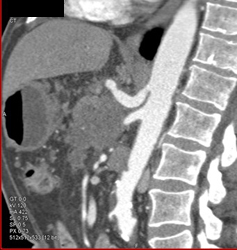

Intraductal Papillary Mucinous Neoplasm (IPMN) Replaces the Entire Gland